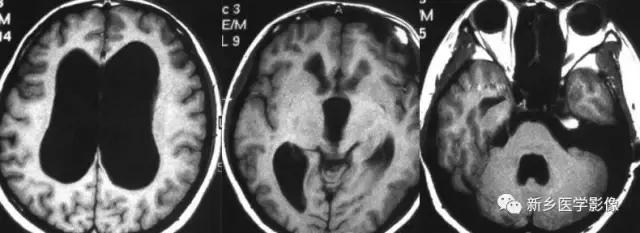

(3)无脑回和巨脑回

无脑回和巨脑回是一组因神经元移行异常所致的脑回发育异常。巨脑回也称平滑脑。巨脑回指有部分脑回存在,这些脑回异常增大增宽.脑沟变浅。巨脑回主要位于额、颞部。无脑回上要位于顶、枕部。

临床上,无脑回和巨脑回畸形患儿均表现有小头畸形和轻微的面部异常,完全无脑回畸形常在两岁前死亡.不完全无脑回畸形存活常能长期。

CT和MR均能够很好显示无脑回和巨脑回畸,表现为大脑半球表面几乎呈光滑状,仅可见少数宽阔、粗大、平坦的脑回,脑沟缺如.脑灰质增厚,脑白质变薄,灰白质分界面异常平滑,见不到白质向灰质内伸入的现象。常见透明中隔腔存在.侧脑室扩大,蛛网膜下腔增宽。